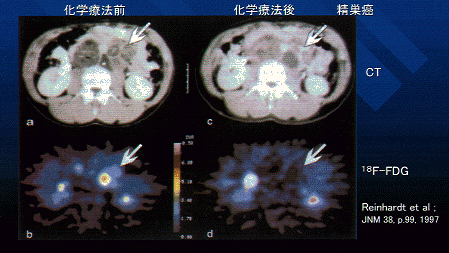

図3 23歳の精巣癌患者における腹腔内腫瘤の例 この患者は、精巣に悪性腫瘍を疑われ、腹部に疼痛を伴う腫瘤が認められた。化学療法前のCT像(a)では、腹腔に不均一な腫瘤が認められ、18F-FDG像(b)でも当該部分に不均一かつ高い集積を認めた。シスプラチン・エトポシド・ブレオマイシンによる治療を3サイクル行った後再度CT検査したところ、腫瘍の一部は縮小したが、他の部分はむしろ増大したように見えた(c)。一方18F-FDG検査では、すべての部分で集積が低下した(d)。この患者は、手術の結果腫瘍の再発ではないことが確認された。これは、CTでは分からない腫瘍の状態が18F-FDGで的確に診断された例である。(原論文1より引用。 Reproduced from by permission of the Society of Nuclear Medicine from: M.J. Reinhardt, V.G.G. Mueller-Mattheis, C.D.Gerharz et al. FDG-PET evaluation of retroperitoneal metastases of testicular cancer before and after chemotherapy; J. Nucl. Med. 38, p.99-101, 1997, Figure 2 (p.100). )